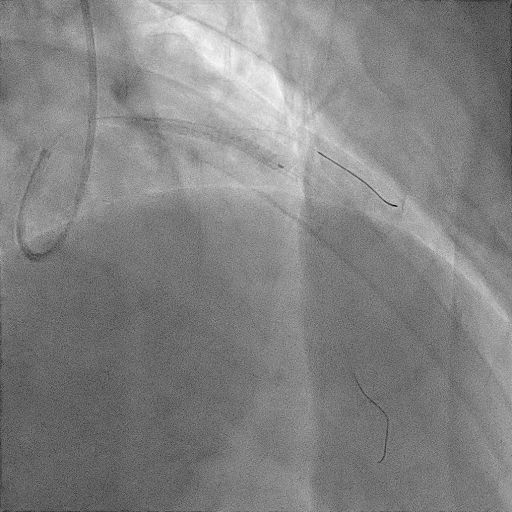

시술이 준비되는 동안, 적절한 산소공급과 함께 수액공급을 하고 관상동맥조영술을 하기 위해 두가지 항혈소판제와 heparin이라는 항응고제를 투약하였다.

대략 40~50분정도가 지났을 때(혈액검사 결과도 안 나올 시간..) 환자는 관상동맥 조영술을 받으러 혈관조영실로 갈 수 있었다.

병변의 위치에 중재술을 마친 환자는 시술 후 합병증 발생여부 및 치료를 위해 중환자실에 입원을 하였다.